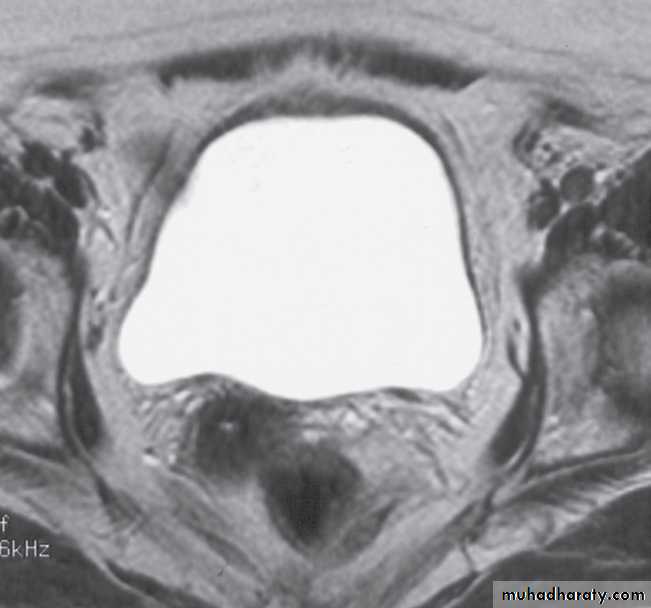

-To assess the extent of bladder or prostate cancer prior to consideration for surgery.

As with CT and ultrasound, the renal contours should be smooth. Corticomedullary differentiation is best seen on T1-weighted images and immediately following intravenous contrast enhancement with gadolinium .The renal collecting systems, ureters and bladder are best seen on T2-weighted images, as the fluid returns a high signal intensity .